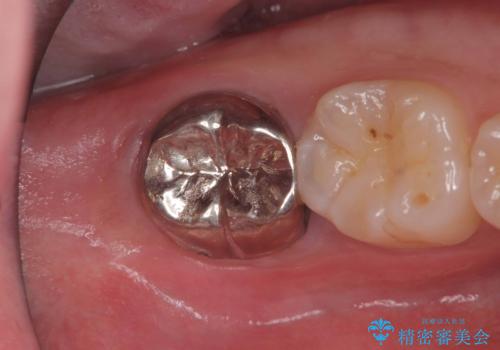

低侵襲なインプラント|痛くないインプラント|エンドペリオ病変|虫歯治療|セラッミクインレー

銀歯を白くしたい|オールセラミッククラウン